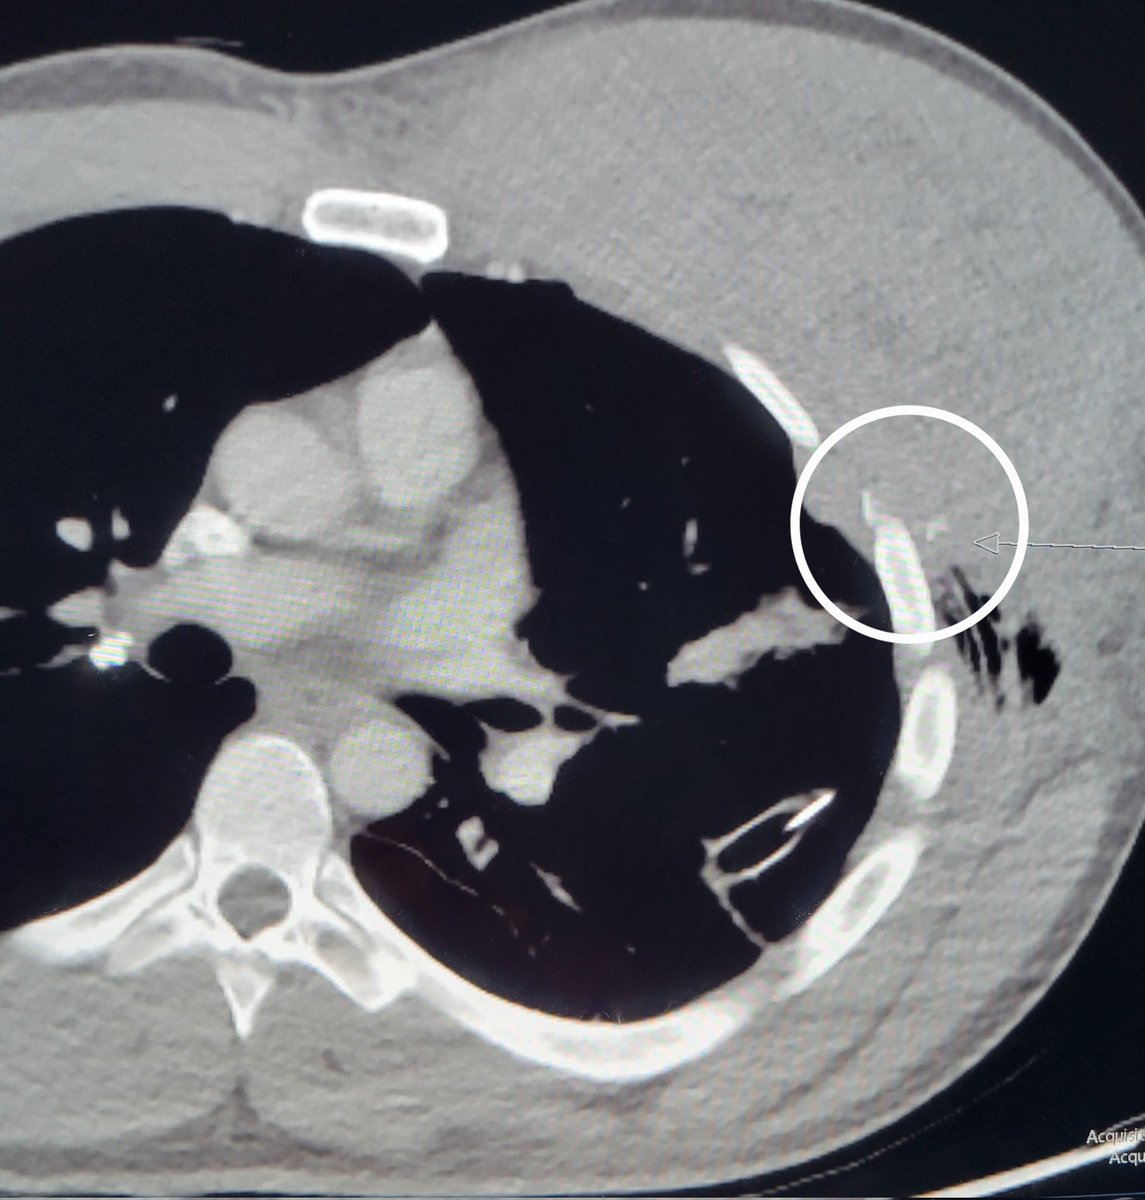

Patient w/ stab wound to chest. CT shows large hematoma with active bleed. Initial angio of intercostals and int mammary was neg. Finally, bleed found off lateral thoracic. Nice hunting Dr. Derek Lee @IanSLeopold! Great read @BlachyDavila Dr. Graf @TempleRadRes @templechestrads